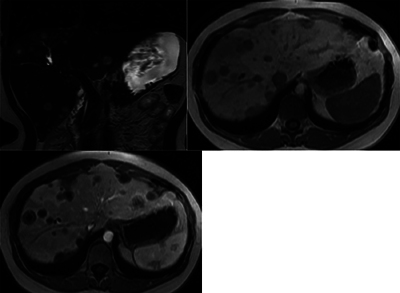

Abstract Image

Teaching point: When confronted with multifocal "metastasis-like" liver lesions without a known primary tumor, in particular in younger female patients, considering hepatic epithelioid hemangioendothelioma (HEHE) in the differential diagnosis can guide pathological examination and potentially avoid the need for multiple invasive biopsies.